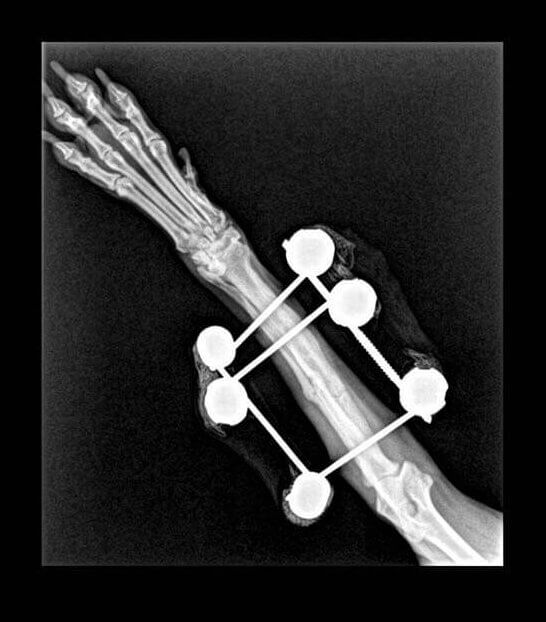

Atès que tot l’examen físic general era normal, li vam realitzar una radiografia. Tal com el propietari s’imaginava, Lluna tenia una fractura a nivell de la diàfisi mitjana del cúbit i el radi (avantbraç).

En aquest cas es va decidir utilitzar uns fixadors externs per donar estabilitat a l’articulació ja que els teixits al voltant de la zona de fractura estaven inflamats i podrien donar problemes de cicatrització si s’hi havia d’incidir per col·locar una placa d’osteosíntesi.